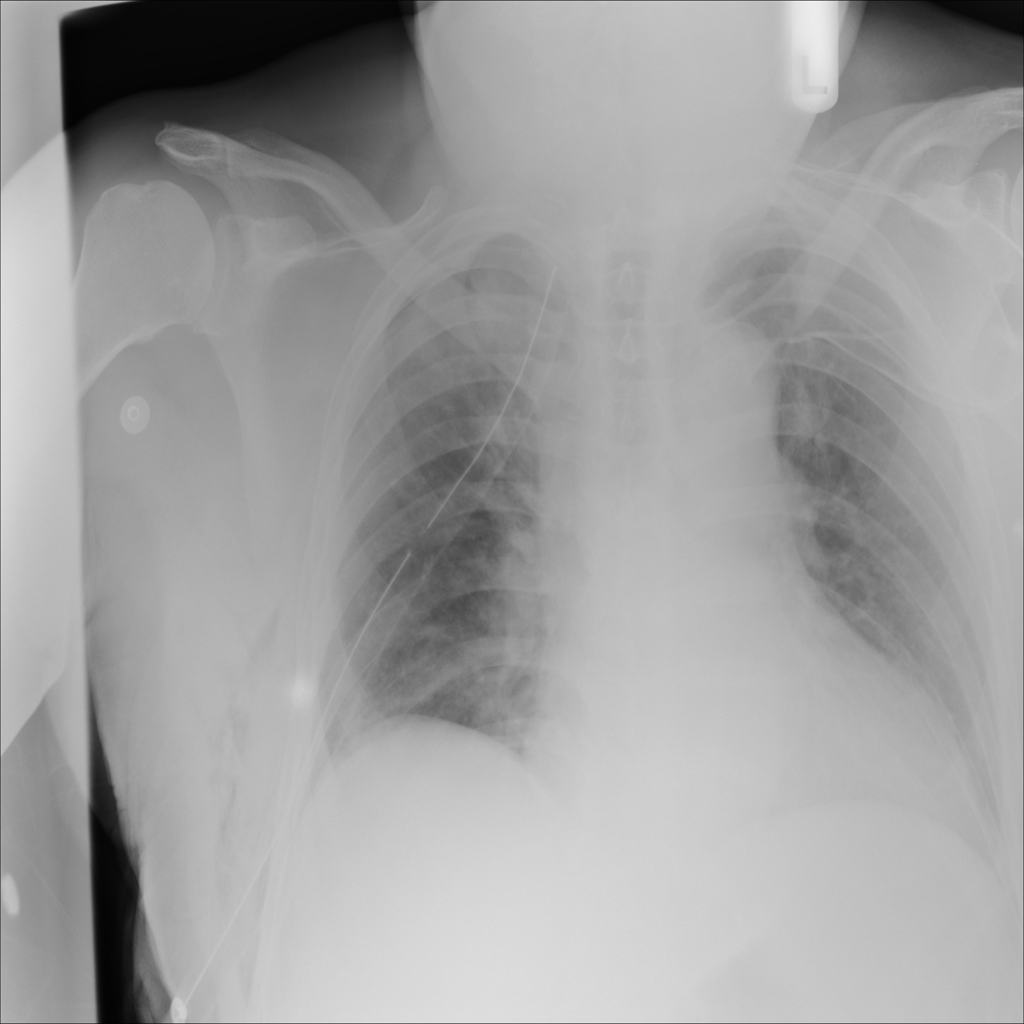

PAT-894B · IMG-000Emphysema

PAT-894B · IMG-000

PA